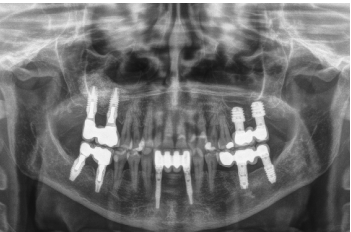

En el año 2007, con los implantes cortos sin pleno desarrollo y sin estudios que demostraran la importancia del diámetro frente a la longitud del implante el protocolo terapéutico para estos casos era muy diferente (Figuras 5-7), centrándose los esfuerzos en la búsqueda de un anclaje por longitud del implante en lugar de buscar la estabilidad bicortical (vestibular-lingual) que realizan los implantes cortos y anchos. Durante este tiempo se produce también

el fracaso de los molares 46 y 47 que deben ser extraídos y reemplazados por implantes dentales.

Una vez transcurridos seis meses tras la colocación de los implantes, se procede a la confección de la prótesis definitiva, en este caso mediante un puente cementado. Este protocolo protésico tampoco es el que seguimos actualmente donde prima la estanqueidad, el hermetismo y el empleo de prótesis atornilladas mediante elemento intermedio o transepitelial, pero en ese momento con este tipo de rehabilitaciones y la conformación de un perfil de emergencia “bio” en los pilares era como se terminaban estos casos (Figura 8)13-18. La implementación de los transepiteliales en las prótesis atornilladas abre un nuevo horizonte en la prótesis, cambiando el protocolo de nuestro grupo de trabajo hacia una mejora del sellado implante-prótesis, al mismo tiempo que se reducen los desajustes protésicos (al ser tomada la impresión directamente sobre el transepitelial y no a la conexión del implante) y se mejora la estanqueidad, disminuyendo entre otras cosas, el riesgo de periimplantitis19-20.